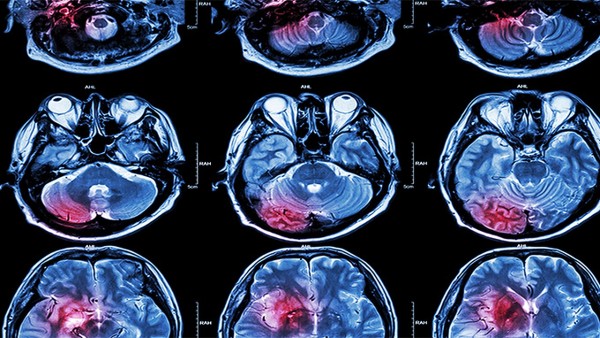

复合脑蛋白水解物片适用于颅脑损伤、脑血管疾病后遗症、记忆丧失和注意力集中障碍的症状改善。它有助于改善脑功能不全,也用于蛋白质缺乏、神经衰弱和一般蛋白质消化吸收障碍的患者。脑蛋白水解物片可以通过血脑保护进入神经细胞,氨基酸在大脑中代谢迅速,半衰期(t1/2)从几秒到几小时不等。